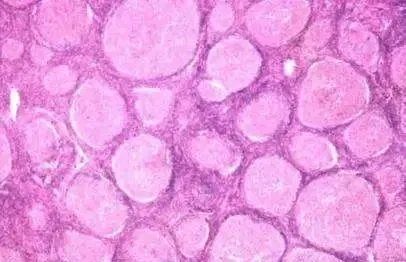

惰性淋巴瘤

对于惰性淋巴瘤,可选用的化疗单药有烷化剂如苯丁酸氮芥、环磷酰胺等药物,有效后停药观察。烷化剂对于进展期的慢性淋巴细胞性白血病(CLL)有肯定的效果。缺点是缓解率低,不能延长患者的生存期。氟达拉滨为核苷类似物中的一种,于20世纪80年代开始用于临床,标准用法为25~30毫克/平方米/天,共用3-5天,静滴,每1月为一个疗程。用于初治慢性淋巴细胞白血病患者的完全缓解率(CR)为38%,部分缓解率(PR)为60%,疗效优于既往其他药物,但是使用2周期如未达PR者,提示预后不佳。氟达拉滨的主要不良反应为:骨髓抑制和免疫抑制,应用后易并发各种条件致病菌感染,部分患者可并发自身免疫性溶血性贫血(AIHA)、免疫性血小板减少性紫癜(ITP)等,老年人使用氟达拉滨应更为慎重。

治疗惰性淋巴瘤的联合用药方案有FC(氟达拉滨+环磷酰胺)、FMD(氟达拉滨+米托蒽醌+地塞米松)、FN(氟达拉滨+米托蒽醌)、CVP(环磷酰胺+长春新碱+泼尼松)或CHOP(环磷酰胺+阿霉素+长春新碱+泼尼松)方案等。对于CD20阳性者,NCCN指南推荐化疗联合利妥昔单抗治疗,结果显示,患者在治疗12个月后其部分缓解率(PR)为89%,利妥昔单抗联合化疗使用可明显提高患者的疗效。目前,层出不穷的新分子靶向药物为治疗惰性淋巴瘤提供了新的选择,相应的临床研究也在如火如茶地进行。